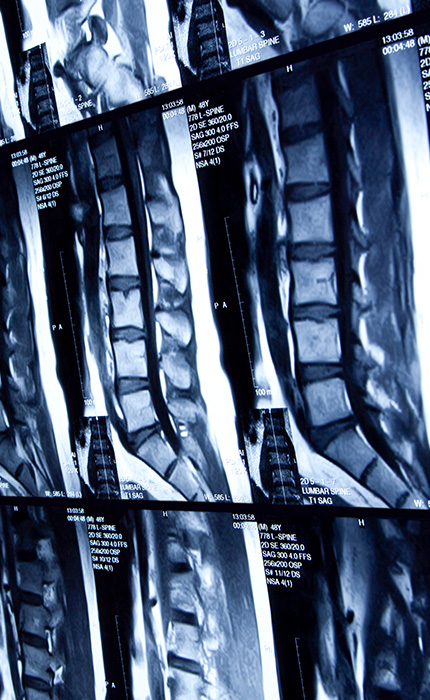

Wirbelsäule

Halswirbelsäule (HWS), Brustwirbelsäule (BWS), Lendenwirbelsäule (LWS)

Die Wirbelsäule ist das zentrale Element für einen aufrechten Gang und für eine unbeschwerte Beweglichkeit. Leider kennen jedoch die meisten Menschen Schmerzen im Rücken und wissen, wie beeinträchtigend diese sein können. Über 60% der Erwachsenen in Deutschland geben an, in den letzten 12 Monaten Rückenschmerzen gehabt zu haben und ca. 15% berichten von chronischen Rückenschmerzen. Am häufigsten ist der untere Rücken bzw. der Nackenbereich betroffen. Frauen leiden häufiger an Rückenschmerzen als Männer, ebenso ältere Personen.

Unsere typische Lebensweise mit mangelnder Bewegung, der Tendenz zum Übergewicht und viele Tätigkeiten im Sitzen tragen zu Schmerzen im Rücken bei. Die Ursachen der Schmerzen können ganz unterschiedlich sein und es muss nicht immer etwas „Schlimmes“ dahinter stecken. Verspannungen und Muskelbeschwerden sind sehr häufig mittels konservativer Therapie (Physiotherapie, Schmerztherapie, etc.) in den Griff zu bekommen. Halten die Beschwerden jedoch an oder kommt es zu Problemen mit dem Fühlen (Sensibilität) und/oder der Kraft der Muskeln, ist eine Bildgebung des Rückens sinnvoll, um zum Beispiel einen Bandscheibenvorfall auszuschließen. Neben den Wirbelkörpern, dem Knochenmark, den Bandscheiben, den kleineren Gelenken zwischen den Wirbelkörpern und den verbindenden Bandstrukturen können auch die Nerven und die Muskulatur gut dargestellt werden. Somit können auch Erkrankungen des Nervenstrangs untersucht werden oder entzündliche Veränderungen der Wirbelsäule.

Eine häufige Basisuntersuchung ist ein Röntgenbild der Wirbelsäule. Ein deutlich detailreicheres Untersuchungsverfahren und für viele Fragestellungen die Bildgebungsmethode der Wahl ist die Magnetresonanztomographie (MRT). Sollte der Fokus auf den knöchernen Strukturen liegen oder gibt es Gründe, welche verhindern sollten, dass ein MRT durchgeführt wird, bietet sich eine Computertomographie (CT) als Alternative an. Für ausgewählte Fragestellungen sind auch nuklearmedizinische Untersuchungsverfahren, wie eine Szintigraphie oder ein PET-CT sinnvoll.